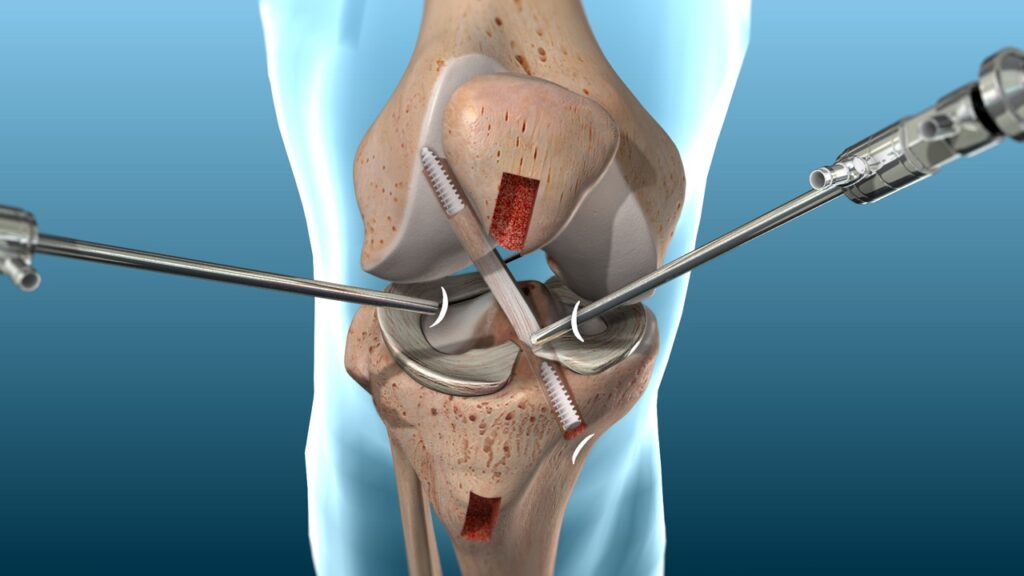

Surgical Procedure:

Preparation: The procedure is typically done under general anesthesia or regional anesthesia. The surgeon will make small incisions around the knee to allow for the insertion of a camera (arthroscope) and surgical instruments.

Graft Harvesting: If using an autograft, tissue will be harvested from the selected donor site (patellar tendon, hamstring tendon, or quadriceps tendon). Allografts are obtained from a donor bank.

Reconstruction: The surgeon will then prepare the area where the ACL is located, remove any remnants of the torn ligament, and drill tunnels into the femur and tibia to insert the new graft. The graft is then secured in place with screws or other fixation devices.

Post-Surgery: The procedure usually takes 1-2 hours. Afterward, the knee is typically bandaged, and a brace is often used to protect the knee during the initial recovery phase.